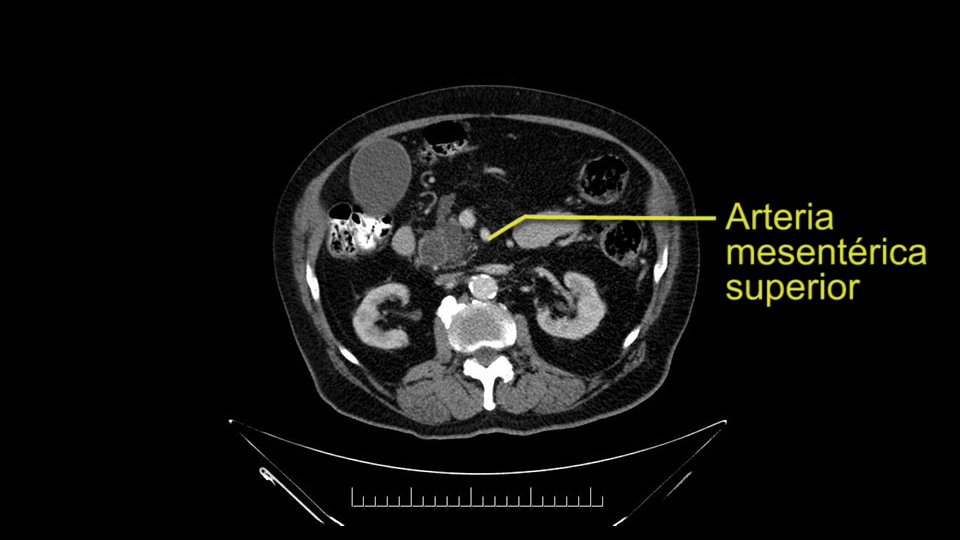

Then either through the coronal or the axial, I’ll do both. Look at the SMA -which is here- I had already looked at it and I don’t see any involvement. There’s the SMA with a nice fat plane between the SMA and the tumor. Over here you can see on the axial, there’s the SMA. Everything on the right side of the SMA has got some nice black around it, which is fat, which means probably no tumor [no tumor, no tumor]. Follow it up to the origin, coming off the aorta. So those are the two technical things that I worry about: the SMA and the SMV.

To plan a pancreatoduodenectomy, we start by reviewing the vascular anatomy, especially the origin of the celiac trunk, here, in front of the aorta, looking for any evidence of stenosis. In addition, we look at the origin of the superior mesenteric artery, to look for any branches, and any replaced right hepatic arteries coming from the superior mesenteric artery; which does occur in about 12% of the population.

Other important points are: the dissection of the uncinate process which must be done very carefully, the ligation of the venous branches there, and looking for the inferior pancreaticoduodenal arteries coming from the superior mesenteric artery during the dissection of the uncinate process.

Para planear una pancreatoduodenectomía, se debe revisar la anatomía vascular, especialmente el origen del tronco celíaco, aquí, por delante de la aorta, buscando areas de estenosis y por otro lado, el origen de la arteria mesentérica superior, para evaluar -sobre todo- si hay ramas, arterias hepáticas derechas provenientes de la mesentérica superior; lo cual ocurre en alrededor del 12% de la población.

Otros puntos importantes por supuesto son: la disección del proceso uncinado, que debe ser muy cuidadosa, la ligadura de las ramas venosas, la búsqueda de la arteria pancreaticoduodenal inferior, proveniente de la arteria mesentérica superior, durante la disección del proceso uncinado.

Once the pancreatic neck is divided, you sort of roll or flip the neck of the gland over, exposing the anterior surface and the right lateral surface of the portal vein-SMV complex. Continue that dissection down. Oftentimes you can really continue your dissection right along the uncinate on the SMA. Again a little advantage of this patient having an ampullary lesion, there's likely to be no evidence of extension into the uncinate so you don't have to worry quite as much about the margin at the uncinate as you would with a pancreatic head cancer. Keeping in mind that you will have an inferior pancreatic duodenal artery in there that you want to try to identify and ligate individually. At some point along that time I go to the ligament of Treitz. Clean an area of the ligament of Treitz of its mesentery, divide it there with a linear stapler. I use the Harmonic scalpel to mobilize the proximal 10-inches or so of small intestine down to the ligament of Treitz completely mobilize the ligament of Treitz past the jejunal limb underneath the root of the mesentery and then carefully dissect the third and fourth portion of the duodenum’s mesentery as well as the remaining uncinate to complete my resection. I will have marked and sent frozen section from the pancreatic neck at the time that I do the resection of that part of the gland so that I have that information back by now. I would also probably get a margin on the uncinate and a margin on the bile duct just for completeness, although for an ampullary carcinoma that would be unlikely to have a positive extension.